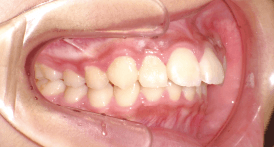

Before Braces - 治療前 -

犬歯と第一大臼歯のⅡ級関係が見られます。

また、前歯に過度なジェットが見られます。